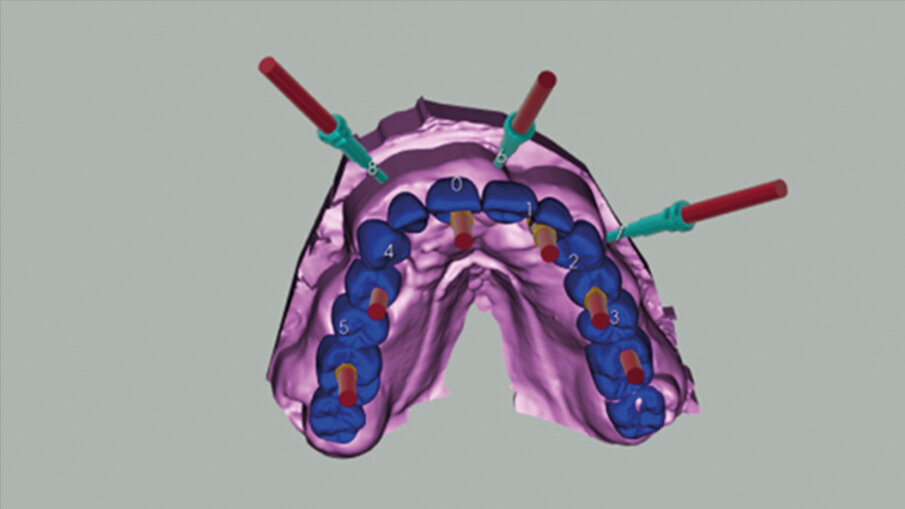

La pianificazione ha previsto innanzitutto l’allineamento all’interno del software dei file DICOM e dei file STL provenienti dalla scansione intraorale (Fig. 5). Il posizionamento degli impianti è stato ragionato in funzione di una ceratura diagnostica preventivamente realizzata con un CAD esterno e importata nel software di chirurgia guidata. Per la riabilitazione dell’arcata superiore, sono stati selezionati 6 impianti intercalati tra i siti post-estrattivi: 3,5 x 13 in posizione 11 e 22, 4 x 13 in posizione 24, 4 x 8 in posizione 26, 4 x 11,5 in posizione 14 e 4 x 10 in posizione 16. Utilizzando le informazioni dei modelli importati (master e ceratura) è stato possibile scegliere preventivamente anche le componenti protesiche in funzione delle emergenze rispetto alla ceratura e allo spessore dei tessuti (Figg. 6-8).